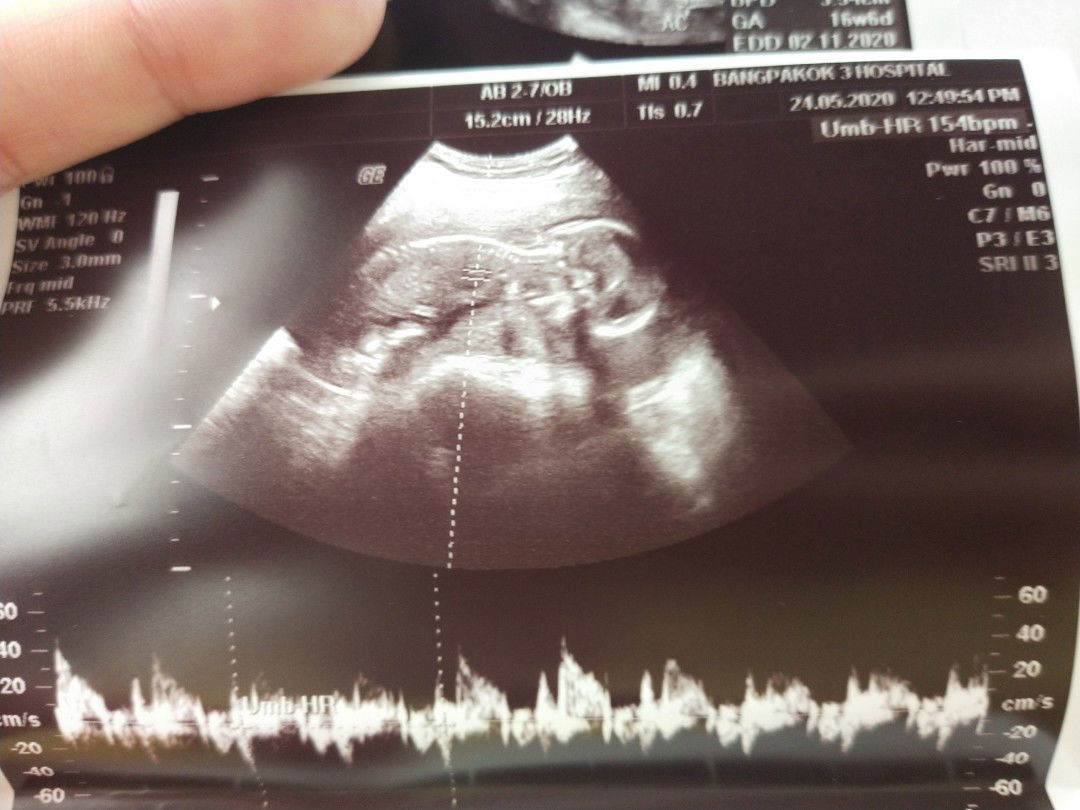

เราจะมาแชร์ประสบการณ์ณการคลอดค่ะ เราเริ่มปวดท้อง 4โมงเย็นของวันที่ 22/10/63 แต่คลอดตอน ตี3.40 น. โดยการผ่าคลอด ตอนแรกเราต้องเท้าความ แม่สามีเราเป็นคนชอบเที่ยวช๊อปปิ้งก็พาไปเดินห้างตลอดมดลูกเกาะต่ำ มีเลือดออกมาซิบๆ หลายวัน พอไปพบหมอหมอบอกอย่าเครียด อย่าทำงานเยอะ ต่อมาเราก็ไม่ได้ทำงานแต่ยังคงเดินห้างเดินตลาดน้ำ เพราะแม่สามีบอกว่าการเดินทำให้คลอดง่ายจนกระทั่งท้องแก่ ไปพบหมอประมาณ 37 wหมอบอกนอนไม่ต้องทำอะไรเลยนะเพราะมานมีสิทธิ์คลอดก่อนกำหนด เราก็ทำตาม พอ 38 w ในวันที่23 ตุลา เราปวดคราย เที่ยงคืนมีมูกเลือดไหลเราก็ บอกแฟนว่าได้เวลาคลอดล่ะที่เตรียมตัวไว้คือคลอดธรรมชาติ แต่แล้วสิ่งที่ไม่ขาดฝันคือ ปากมดลูกเปิด 6 ซม.แต่ลูกไม่ยอมเคลื่อนตัวมาที่เชิงกราน เสียงหัวใจเต้นแพร่วลง แม่ชิว (มีอาการหนาวสั่นความดันสูง เสี่ยงช๊อต) เลยเอาเข้าห้องผ่าตัดก่อนอื่นมห้เราวัดความดัน เราก็หนาวสั่นแบบนั้นโค้งตัวในท่านั่งจนเห็นกระดูกข้างหลังให้ได้มากที่สุดเพื่อบล๊อคหลังพอบล๊อคแตกต่างจากที่รอคลอดธรรมชาติโดยสิ้นเชิง เพราะมานเหมือนเป็นอัมพาตช่วงล่างไปเลยจากนั้นเค้าก็ผ่าโดยที่เราไม่รู้อะไร แต่พอหมดลิทธิยาในวันที่สองปวดมากทรมารก็ต้องลุกยืนน้ำนมไม่ได้อีก แต่ลูกก็ออกมาปลอดภัยค่ะแต่ต้องพยายามเคร่งน้ำนมให้ลูก #อยากคลอดเอง #คลอดเองฝืนตัวไวกว่าผ่า #ผ่าตัดพักฝืนนาน